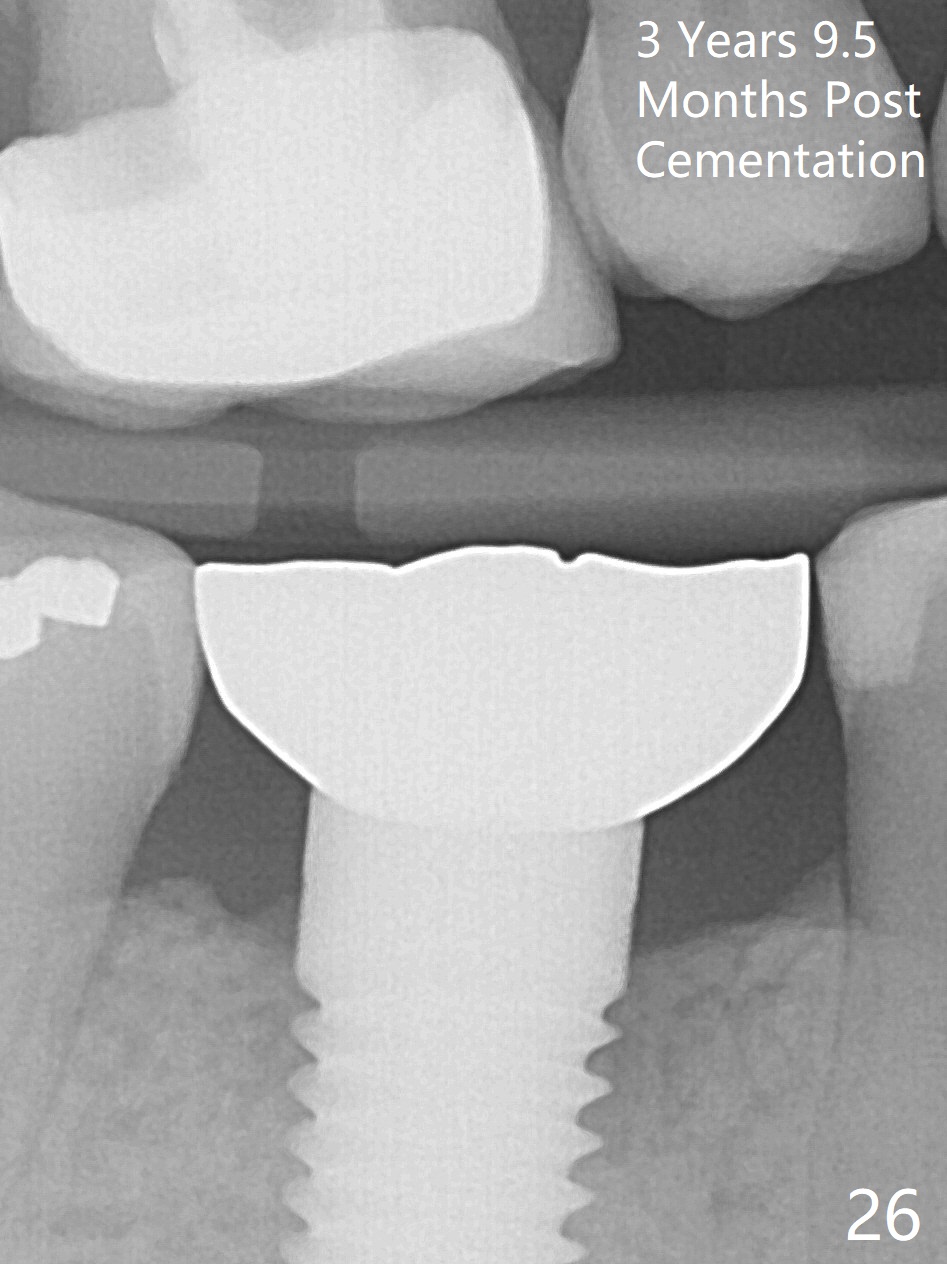

The patient will return for immediate implant at #14. Do not forget placing an implant as palatal as possible. There is no sign of infection at #30 three years 9.5 months post cementation because of water pik for #3 endo failure (Fig.25,26).